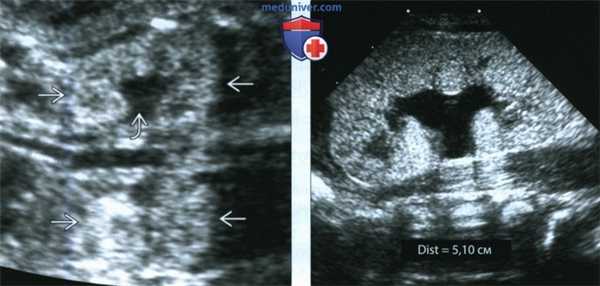

(Слева) УЗИ во фронтальной плоскости. Не совсем типичная ультразвуковая картина. Почки крупные, гиперэхогенные, содержат гипоэхогенные пирамиды. Умеренное расширение лоханки. При прогрессировании заболевания картина может измениться.

(Справа) Тот же случай. Постнатальное УЗИ во фронтальной плоскости. Более типичная картина: паренхима диффузно гиперэхогенная, утрачена нормальная структура мозгового вещества. Данный случай иллюстрирует разнообразие ультразвуковых находок при АРПКП.

2. УЗИ при аутосомно-рецессивном поликистозе почек у плода:

• Размеры почек >2 стандартных отклонений выше средних для ГВ:

• Почки могут быть диффузно гиперэхогенными или иметь гиперэхогенные пирамиды

• Могут визуализироваться кисты, однако они не преобладают

• С помощью современного оборудования с высоким разрешением тубулярную эктазию можно обнаружить в III триместре

• Нормальная гипоэхогенная кора сохранена, но при тяжелом течении различить ее трудно

• Маловодие

• Мочевой пузырь плода может не визуализироваться (олигурия)

• Гипоплазия легких

(Слева) Другой случай АРПКП. УЗИ в сагиттальной плоскости. Визуализируются увеличенные гиперэхогенные почки (калиперы). Нормальная гипоэхоген-ная кора сохранена. Это довольно характерная находка, но обнаружить ее на пренатальном УЗИ бывает трудно.